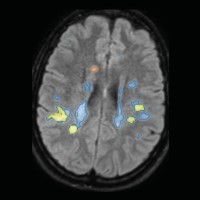

Das Modul Läsionscharakterisierung erleichtert die Differentialdiagnostik und Verlaufskontrolle bei MS- und Demenz-Patient:innen. Ermöglicht wird dies durch eine vollautomatische Segmentierung von Läsionen der weißen Hirnszubstanz.